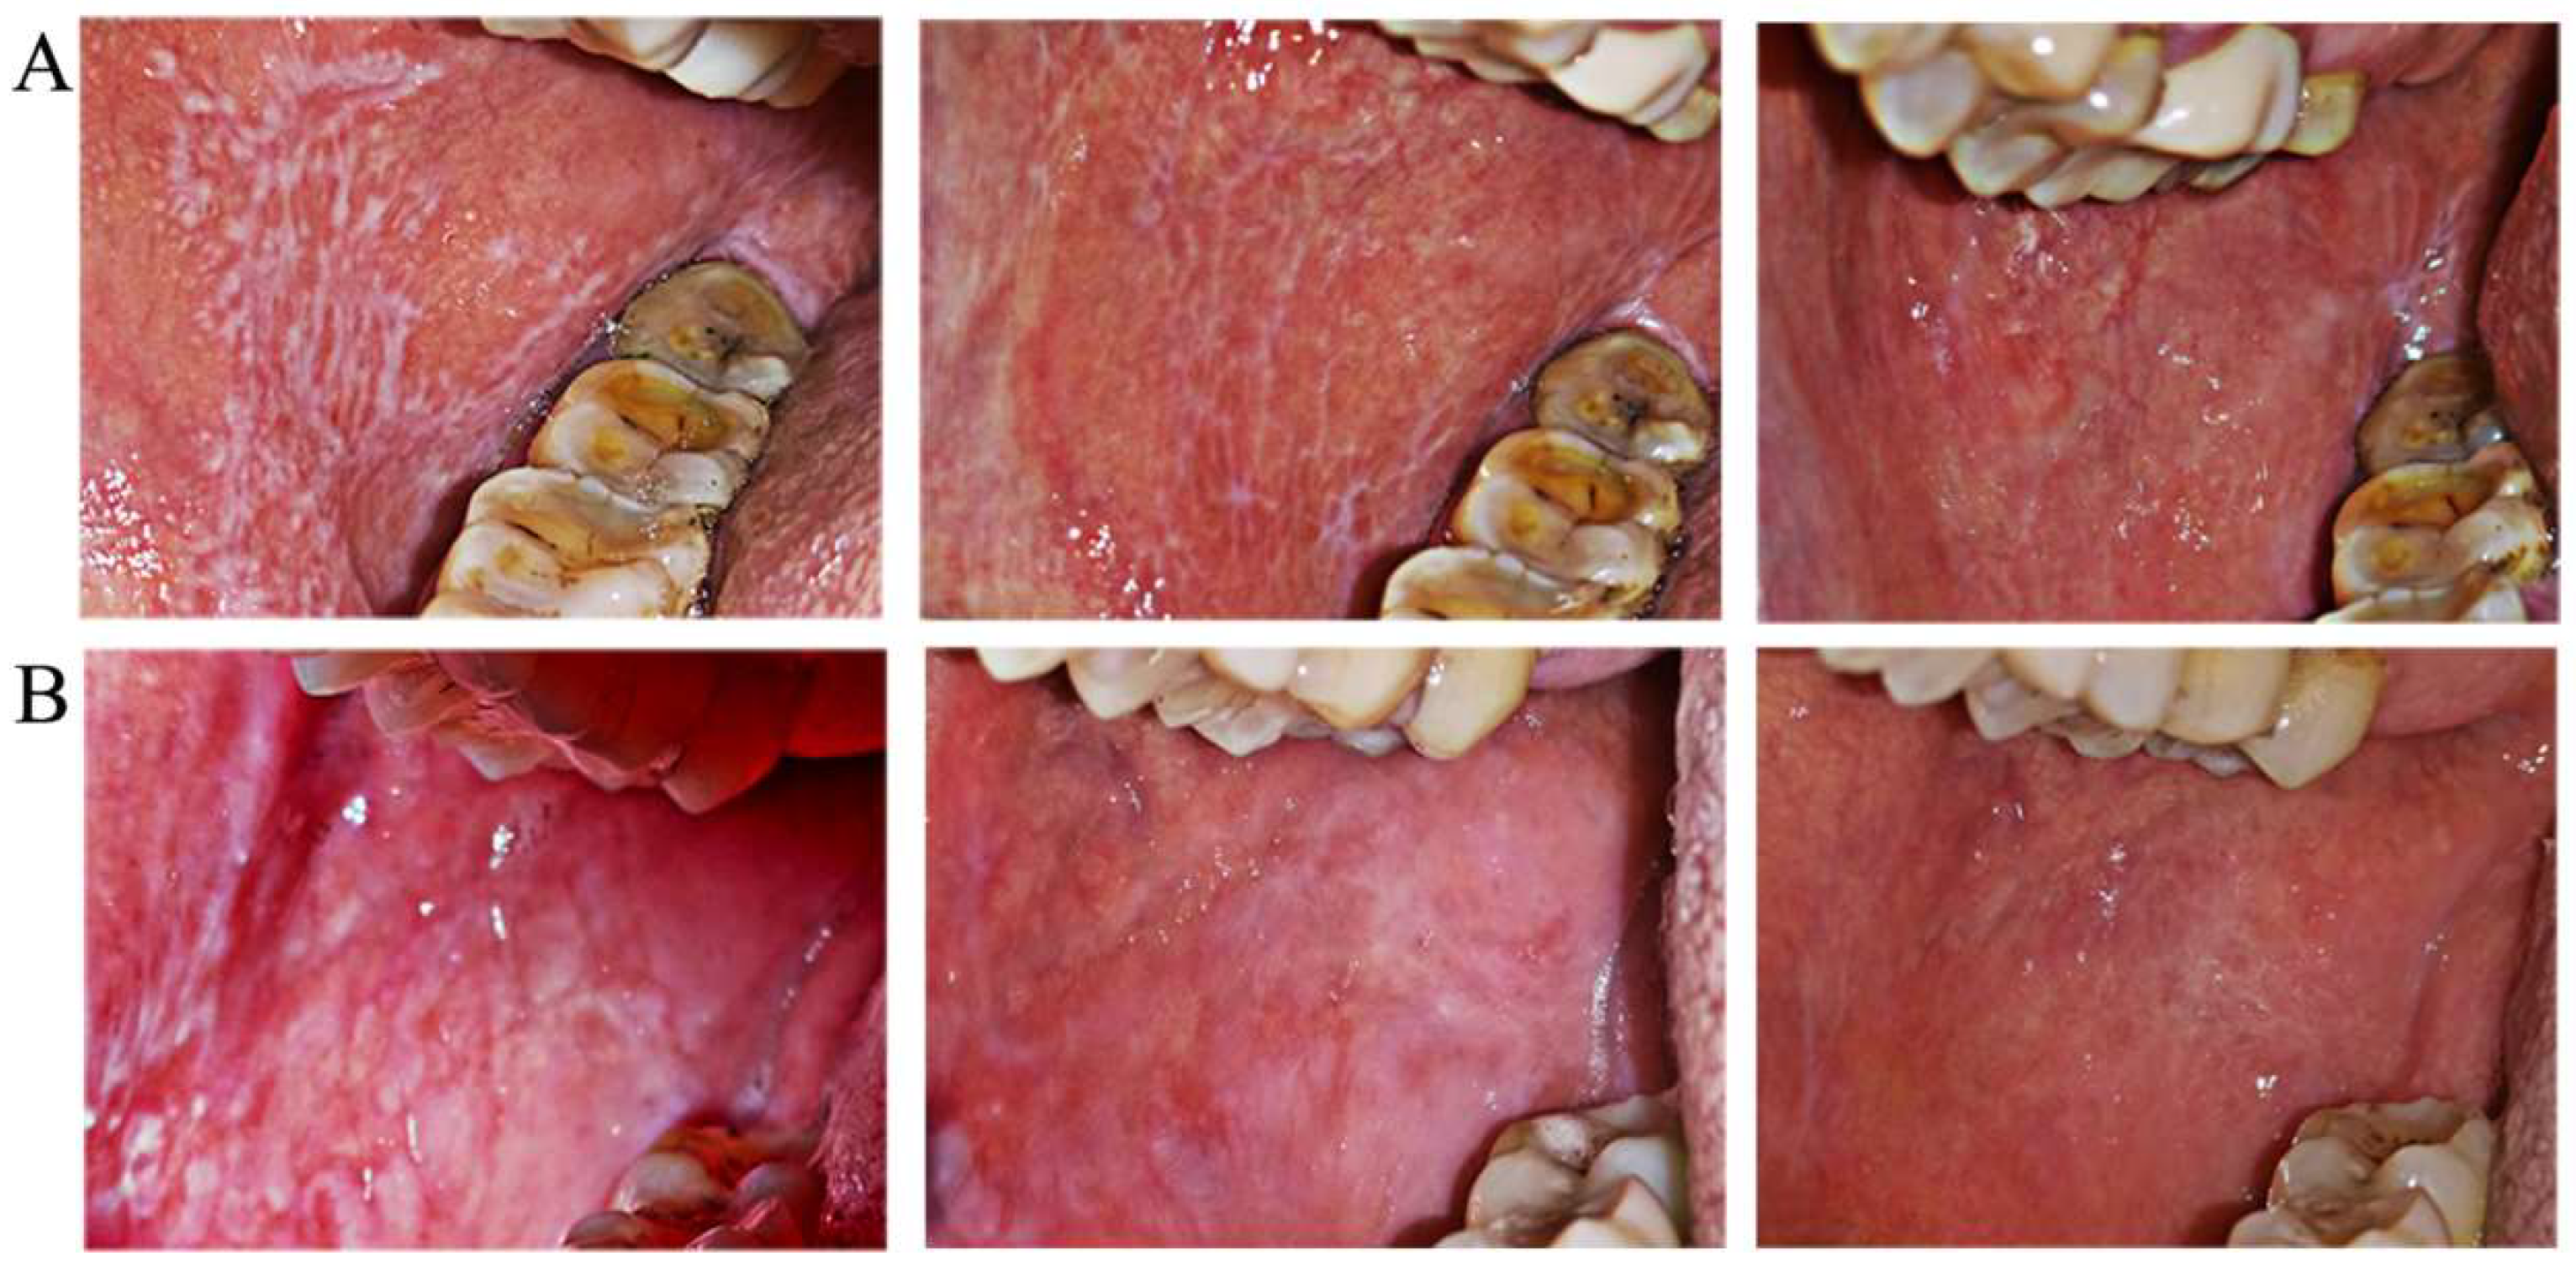

There was no significant difference in pretreatment sign scores and VAS between the groups with non-erosive OLP. From 2 weeks to 6 months after treatment, sign scores changed gradually in both groups, with no significant recurrence in either Group A or B, and there was no significant difference between groups A and B (Figure 3A). In terms of pain relief, VAS in Group B showed improvements at 1 month and significant relief at 6 months, while VAS in Group A indicated relief at 3 months, which was maintained at 6 months. The degree of VAS relief in Group B was more obvious than that in Group A, but the difference was not significant (Figure 3B). Two clinical examples of Groups A and B with non-erosive OLP are shown in Figure 4. The treatment outcomes were assessed in both groups with non-erosive OLP at 2 weeks and 1, 3, and 6 months of treatment (Table 6). There was no difference in the effective rate between the two groups (50.0% vs. 44.4%, 70.0 vs. 77.8%, 80.0% vs. 88.9%, and 80.0% vs. 88.9%).

Figure 4.

Magnitude of clinical responses of non-erosive OLP to dexamethasone plus gentamycin mouthwash (A) and dexamethasone plus gentamycin mouthwash combined with TGP capsules (B). The left panel is the clinical presentation at the initial baseline, the middle panel is the clinical presentation at the 1-month follow-up, indicating improved white lesions, and the right panel is the clinical presentation at the 6-month follow-up, when only a few white lesions remained (upper, Group A) or they had disappeared (upper, Group B).